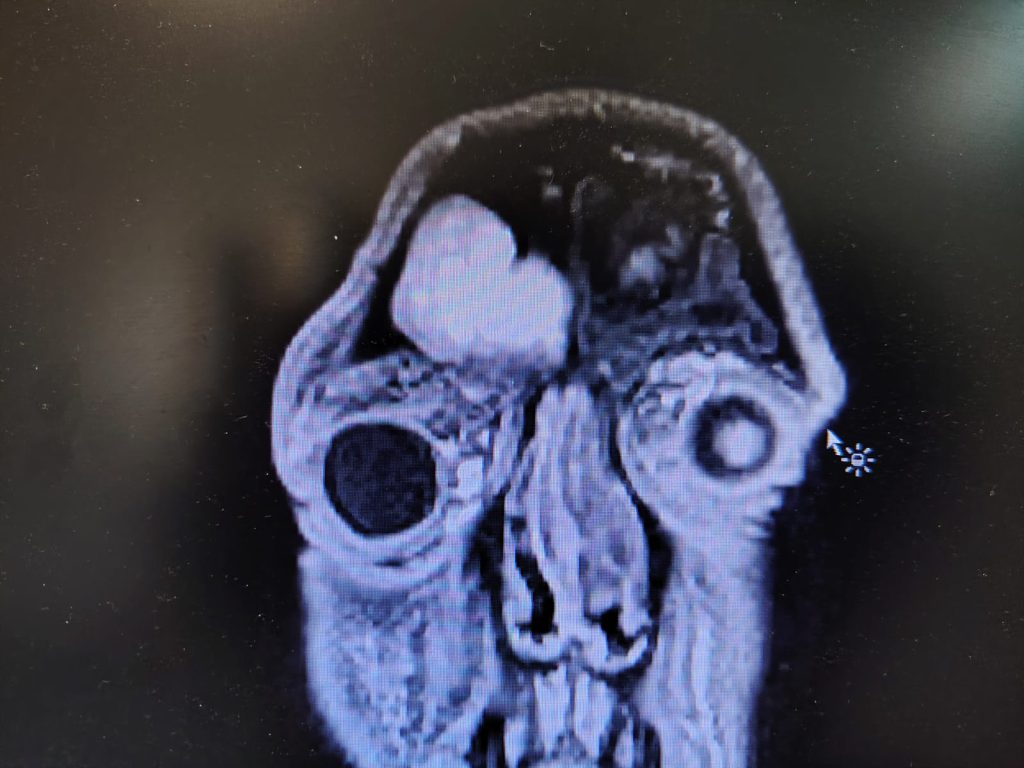

Aveva accumulato muco fino alla cavità dell’occhio per una grave sinusite e aveva perso l’80% della vista. Grazie a un intervento d’urgenza al Policlinico di Bari, un uomo di 37 anni ha recuperato completamente la vista, compromessa dalle complicanze di un accumulo di pus all’interno del seno frontale che, non potendo defluire attraverso il naso, aveva forato la parete superiore del tetto dell’orbita andando ad accumularsi nella cavità dell’occhio. Il paziente, a causa dello stiramento del nervo ottico, aveva serie difficoltà nella vista oltre a mal di testa e un gonfiore alle palpebre quando è arrivato all’Unità operativa di Otorinolaringoiatria, diretta dal prof. Nicola Quaranta. L’esame al cranio, eseguito nella precedente struttura di cura, aveva documentato come tutti seni paranasali fossero completamente chiusi per infiammazione. Nel seno frontale destro c’era una massa che lo riempiva del tutto e che aveva intaccato l’osso vicino, arrivando a estendersi verso l’area dell’occhio. Dopo l’arrivo al Policlinico, l’uomo è stato sottoposto a una nuova valutazione che mostrava la perdita dell’80% della vista. L’équipe ha eseguito un intervento combinato mediante tecnica endoscopica, eseguita dai dottori Berardi e Nicola De Candia, e approccio esterno transcranico con accesso sopraccigliare, eseguito dal dottor Luigi Madami, con il supporto dell’anestesista Michele De Michele e la collaborazione del medico in formazione specialistica Leo Victor Tedone. “L’utilizzo di questa tecnica – spiega il dott. Madami – ha permesso di liberare la fossa nasale dalle recidive e dalle aderenze, la via esterna ha permesso di drenare gli ascessi della cavità orbitaria e del seno frontale e di ricreare nuova comunicazione fra il seno frontale ed il naso. Dopo 48 ore, una nuova valutazione oculistica ha documentato una ripresa totale del visus che ritornava ai 10/10. Un recupero completo della vista”.